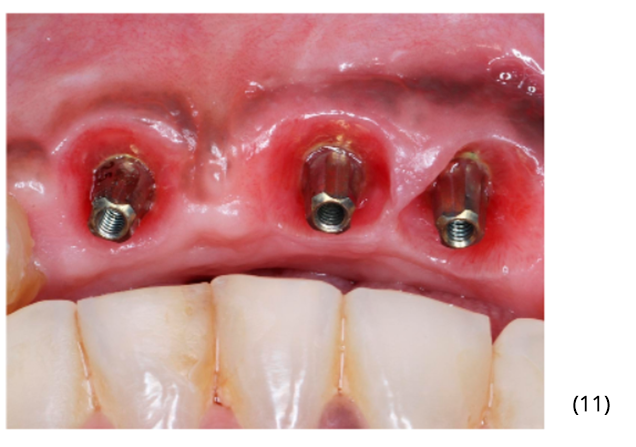

Utilizamos três munhões do tipo Ideale – Implacil De Bortoli de altura 3.3×2.5×4 mm para confecção das próteses do tipo parafusada (imagens 10 e 11). A foto final foi no acompanhamento de seis meses, onde podemos observar ótima estabilidade do tecido peri-implantar (imagem 12).